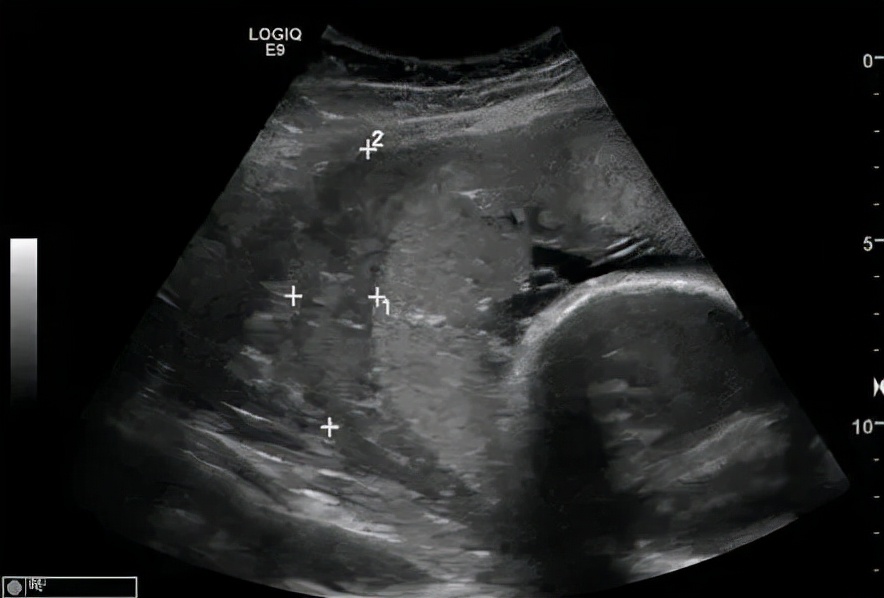

孕检是保证胎儿正常发育的重要手段。通过彩超检查,尤其羊水过多的孕妇,可早起发现胎盘异常的情况,避免胎盘早剥的发生。